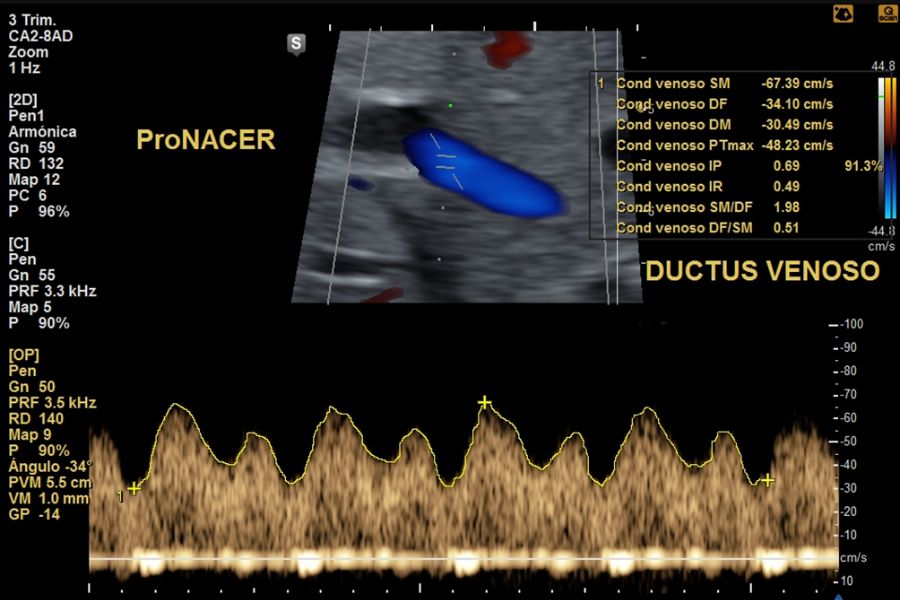

Doppler fetoplacentario